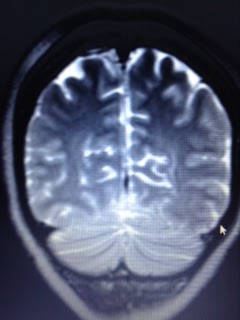

| June 2014 MRI. Neurosurgeon says some of the white space ( top left corner ) is scar tissue from my brain injuries. |

| My brain looks like a walnut. |